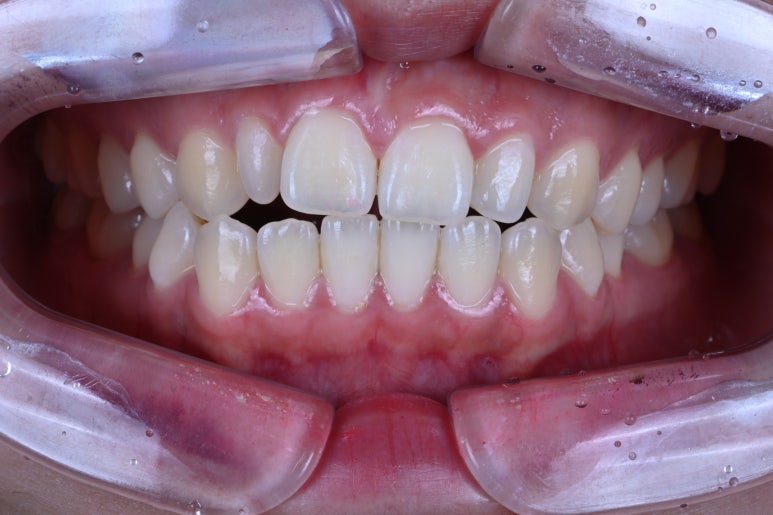

환자분이 오셨습니다. 왜소치가 어느 치아인지 딱 봐도 아시겠죠?

바로 이 녀석입니다!

치아가 폭도 작고 길이도 짧고.. 이 녀석 때문에.. 환자분이 고민이 이만저만이 아닙니다.